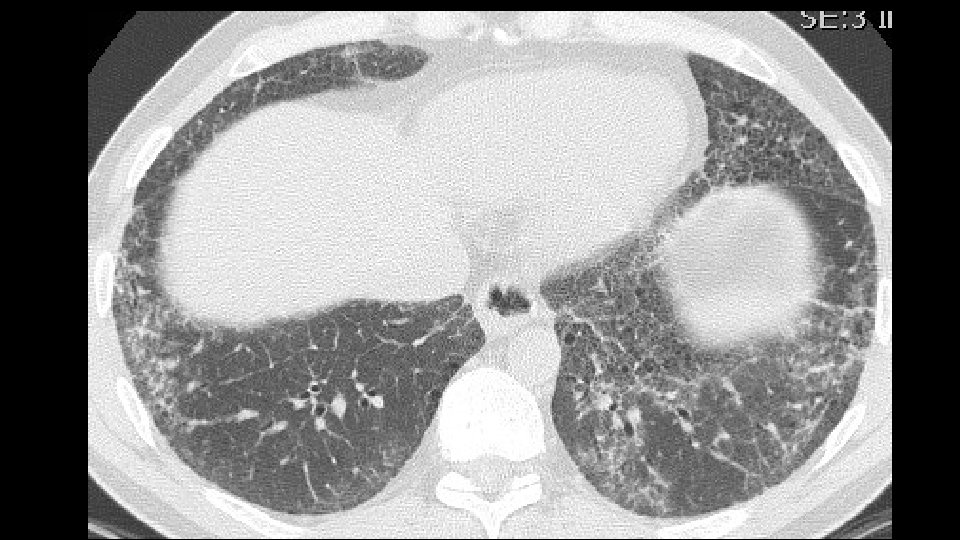

1. Mechanical stress and remodeling are highest in that areas in which traction bronchiectasis and honeycombing appear. Carloni A. et Al. Journal of theoretical biology 2013 2. Most of the "scarred" tissue is in the region distal to the traction bronchiectasis, beneath the pleura and does not concentrically surround the dilated bronchi. 2007 Score 1 bronchiectasis 2014 2010 Score 3 bronchiectasis Honeycombing

3. In Nonspecific Interstitial Pneumonia (NSIP), traction bronchiectasis are completely surrounded by the fibrotic tissue Fibrotic NSIPof the years NSIP in the course a 2009 b 2013